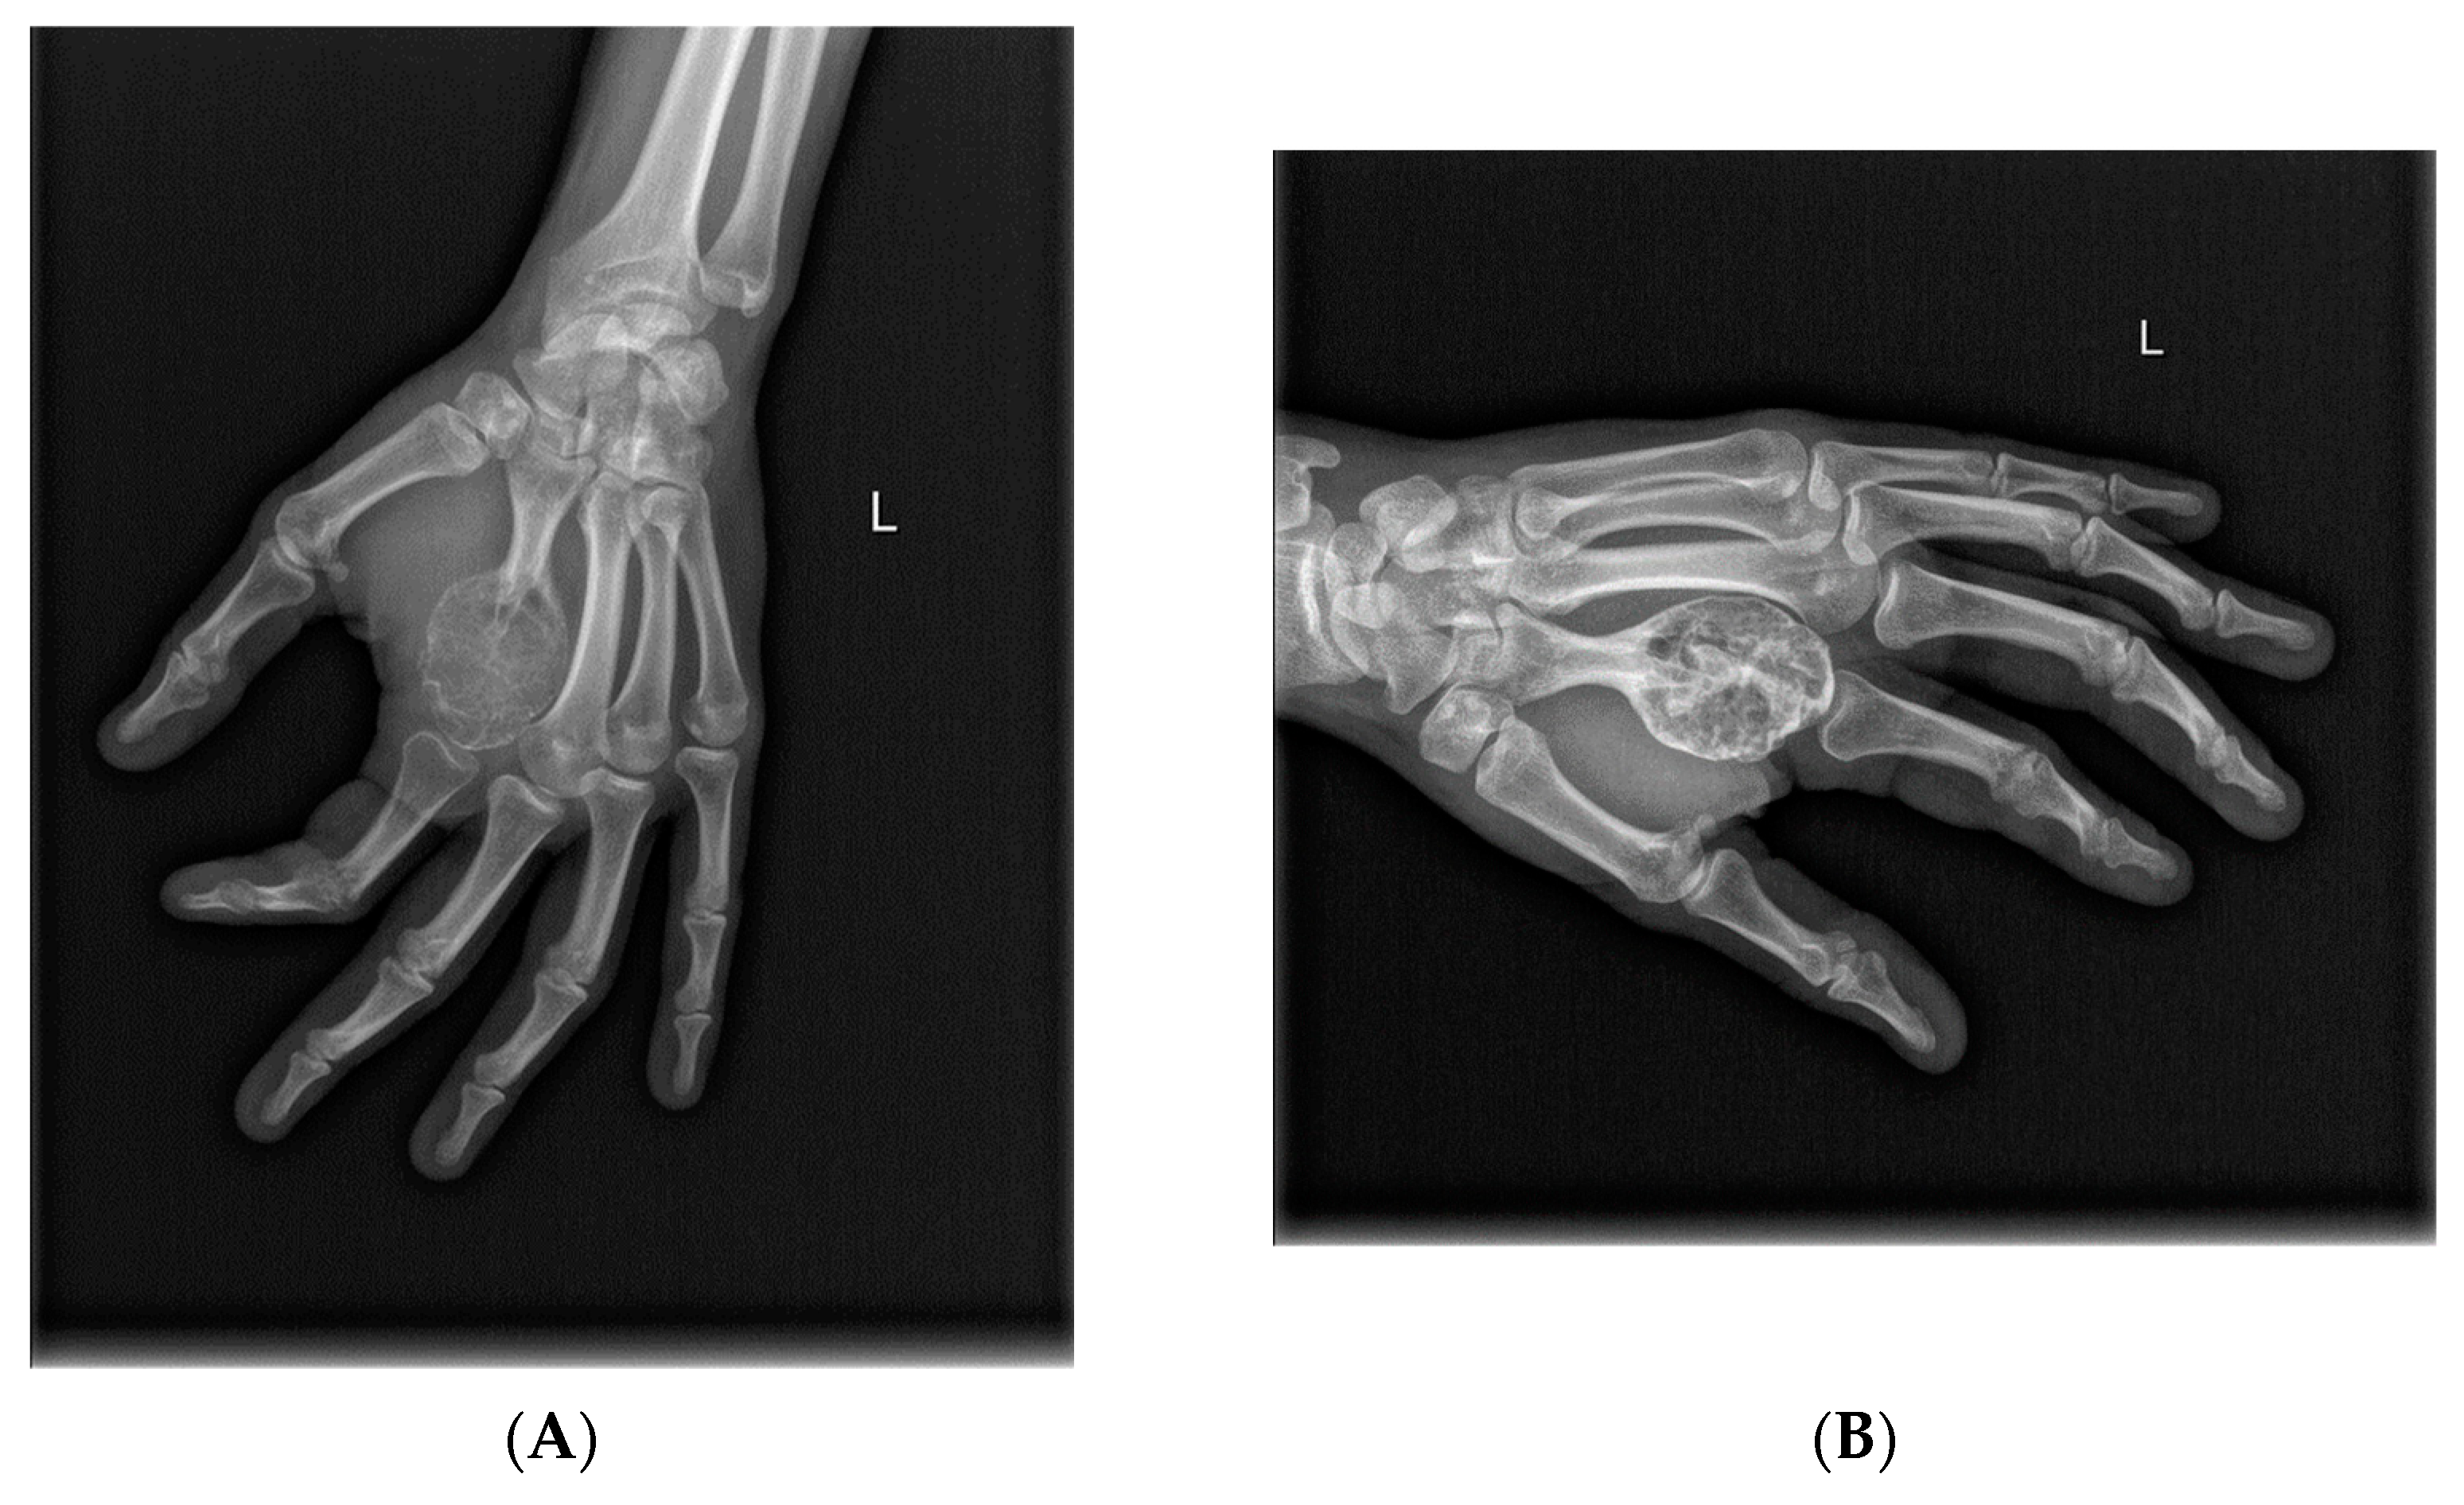

- Van Langevelde, K.; McCarthy, C.L. Radiological findings of denosumab treatment for giant cell tumours of bone. Skelet. Radiol. 2020, 49, 1345–1358. [Google Scholar] [CrossRef] [PubMed]

- Murphey, M.D.; Nomikos, G.C.; Flemming, D.J.; Gannon, F.H.; Temple, H.T.; Kransdorf, M.J. Imaging of Giant Cell Tumor and Giant Cell Reparative Granuloma of Bone: Radiologic-Pathologic Correlation. RadioGraphics 2001, 21, 1283–1309. [Google Scholar] [CrossRef]

- Oguro, S.; Okuda, S.; Sugiura, H.; Matsumoto, S.; Sasaki, A.; Susa, M.; Morioka, H.; Jinzaki, M. Giant Cell Tumors of the Bone: Changes in Image Features after Denosumab Administration. Magn. Reson. Med. Sci. 2018, 17, 325–330. [Google Scholar] [CrossRef]

- McCarthy, C.L.; Gibbons, C.L.M.H.; Bradley, K.M.; Hassan, A.B.; Giele, H.; Athanasou, N.A. Giant cell tumour of the distal radius/ulna: Response to pre-operative treatment with short-term denosumab. Clin. Sarcoma Res. 2017, 7, 19. [Google Scholar] [CrossRef]

- Hakozaki, M.; Tajino, T.; Yamada, H.; Hasegawa, O.; Tasaki, K.; Watanabe, K.; Konno, S. Radiological and pathological characteristics of giant cell tumor of bone treated with denosumab. Diagn. Pathol. 2014, 9, 111. [Google Scholar] [CrossRef]